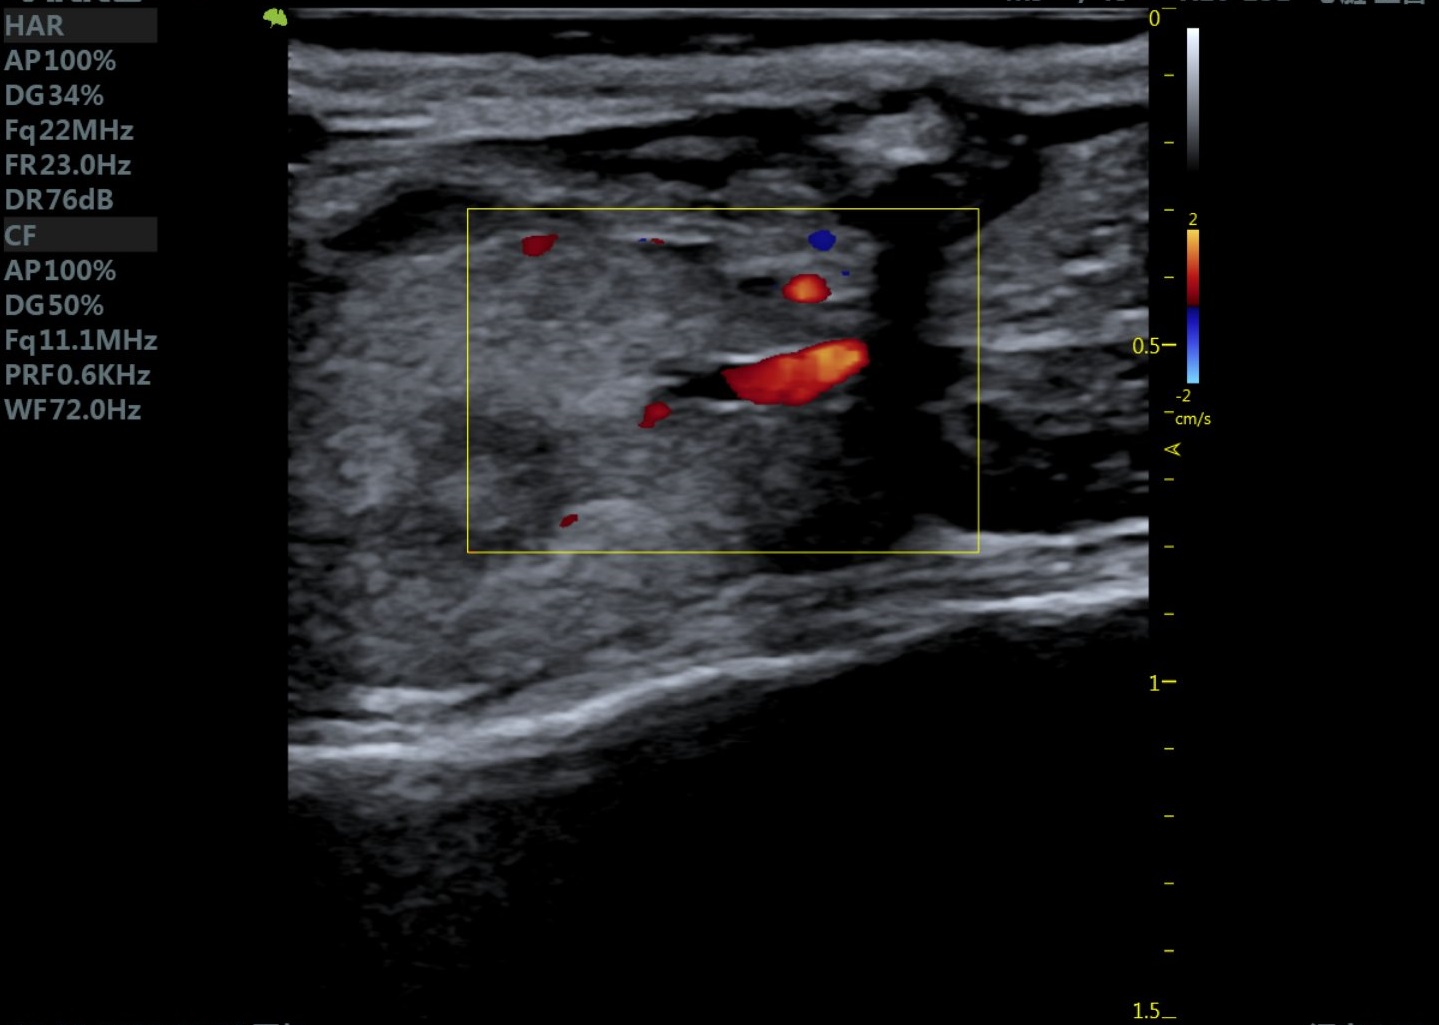

23MHz高频探头,优秀卓越的浅表显影

RF Flow充盈不外溢 Xcen超高频浅表显影

小鼠主动脉弓 小鼠肾脏血流